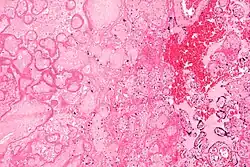

| Micrograph of a placental infarct. H&E stain. | |

A placental infarction results from the interruption of blood supply to a part of the placenta, causing its cells to die.

Small placental infarcts, especially at the edge of the placental disc, are considered to be normal at term. Large placental infarcts are associated with vascular abnormalities, e.g. hypertrophic decidual vasculopathy, as seen in hypertension.[1] Very large infarcts lead to placental insufficiency and may result in fetal death. Placental infarcts are generally detected after birth, although using ultrasound may be a way to notice infarcts prenatally. This method still needs more research and may not be completely effective in noticing infarcts. [2]

Maternal floor infarcts are not considered to be true placental infarcts, as they result from deposition of fibrin around the chorionic villi, i.e. perivillous fibrin deposition.